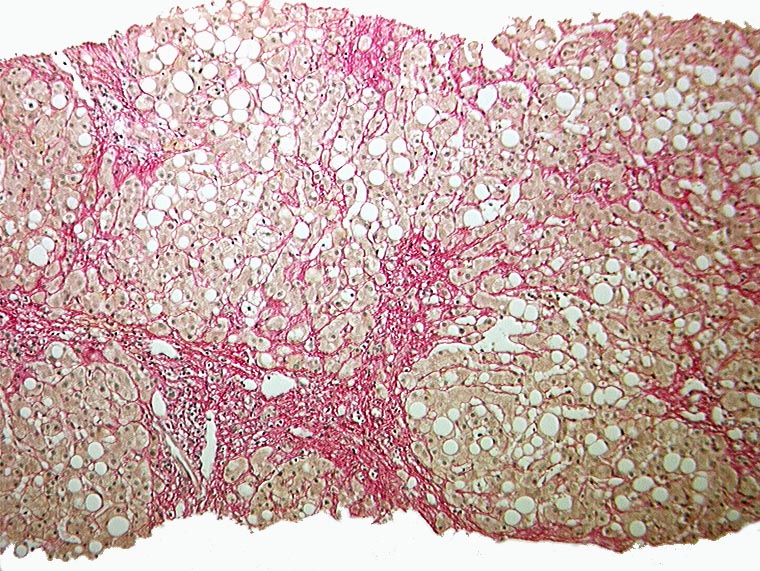

AP/ Floride alkoholische Steatohepatitis

Floride alkoholische Steatohepatitis

Leber